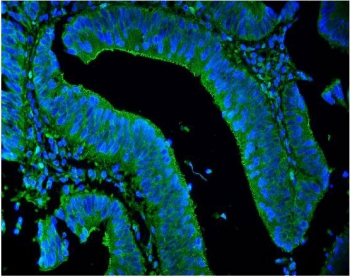

Immunofluorescent staining of FFPE human intestinal cancer with LPP antibody (green) and DAPI nuclear stain (blue). HIER: steam section in pH8 EDTA for 20 min.